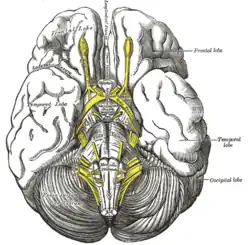

Die Neurologie (von altgriechisch νεῦρον neuron, deutsch ‚Nerv‘, und -logie ‚Lehre‘) ist die Wissenschaft und Lehre vom Nervensystem, seinen Erkrankungen und deren medizinischer Behandlung. Sie stellt seit der zweiten Hälfte des 19. Jahrhunderts ein eigenständiges Teilgebiet der Medizin dar. Die Grenzen zur Psychiatrie und zur Neurochirurgie sind dabei teilweise fließend.

Die in der Neurologie wichtigsten Organsysteme sind das Zentralnervensystem (also Gehirn und Rückenmark), seine Umgebungsstrukturen und Blutgefäße. Dazu kommt das periphere Nervensystem und die Muskulatur, einschließlich der Verbindungsstrukturen zwischen beiden. In Deutschland ist die Neurologie um 1845 mit Moritz Heinrich Romberg als ein Teilgebiet aus der Inneren Medizin hervorgegangen. In den USA, in Großbritannien, Russland und anderen Staaten dagegen hatte sich die Neurologie gleich als eigenständiges Fach entwickelt.[1]

Pyramidenbahnzeichen: Die Pyramidenbahn besteht aus einem Bündel von Nervenzellfortsätzen, die von Stirnhirn bis zu den ersten Umschaltstellen im Rückenmark ununterbrochen durchlaufen. Diese Zellen sind so etwas wie ein Schrittmacher der willkürlichen Bewegungen. Der Name Pyramidenbahn stammt von einer Struktur im Hirnstamm (der pyramis), durch die die Pyramidenbahn hindurchläuft. Wenn dieses Nervenbündel an irgendeiner Stelle unterbrochen wird, kommt es zu einem typischen Funktionsausfall: einer spastischen Lähmung (Kraftminderung mit Muskeltonuserhöhung). Die Ursachen können völlig unterschiedlich sein: Eine Verletzung der Wirbelsäule und des Rückenmarkes, eine Durchblutungsstörung im Hirnstamm, eine Hirnblutung im Bereich der sogenannten Kapsel oder ein Tumor in der Großhirnrinde an der entsprechenden Stelle. Neben der Lähmung und der Muskeltonuserhöhung finden sich dann häufig sogenannte Pyramidenbahnzeichen. Man meint damit in erster Linie das Anheben (Dorsalextension) der großen Zehe beim Bestreichen der Fußsohle an ihrem Außenrand (Babinski-Reflex).